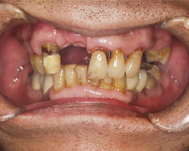

6ヶ月後、歯ぐきを開いて膜を取り除くと、骨がなかった所にしっかりと骨が作られ、インプラントが完全におおわれている状態が判ります。

完成写真

この患者さんの歯茎はもうすでに腐り骨は溶けている状態だったので、骨を再生せずにインプラントを行なうと、写真のように歯茎の上の方からインプラントを入れることになり、非常に不自然な完成となってしまいます。